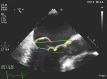

Patients with severe mitral valve regurgitation secondary to degenerative disease are known to benefit from mitral valve repair surgery. Novel techniques for achieving mitral valve repair on the beating heart have been developed and are being introduced into clinical practice. The HARPOON Beating Heart Mitral Valve Repair System (MVRS) in recent studies has demonstrated efficacy and safety for the repair of degenerative mitral valve disease on the beating heart. The device uses transoesophageal echocardiographic guidance to implant artificial expanded polytetrafluoroethylene (ePTFE) cords on prolapsed mitral valve leaflets in the beating heart. It requires general anaesthesia and there are specific intensive care and anaesthesia considerations for the safe management of these cases. This article describes the general principles of intensive care and anaesthesia management employed for the initial patients treated with the HARPOON Beating Heart MVRS, the outcomes for these patients, and the potential challenges for the future management of these cases.